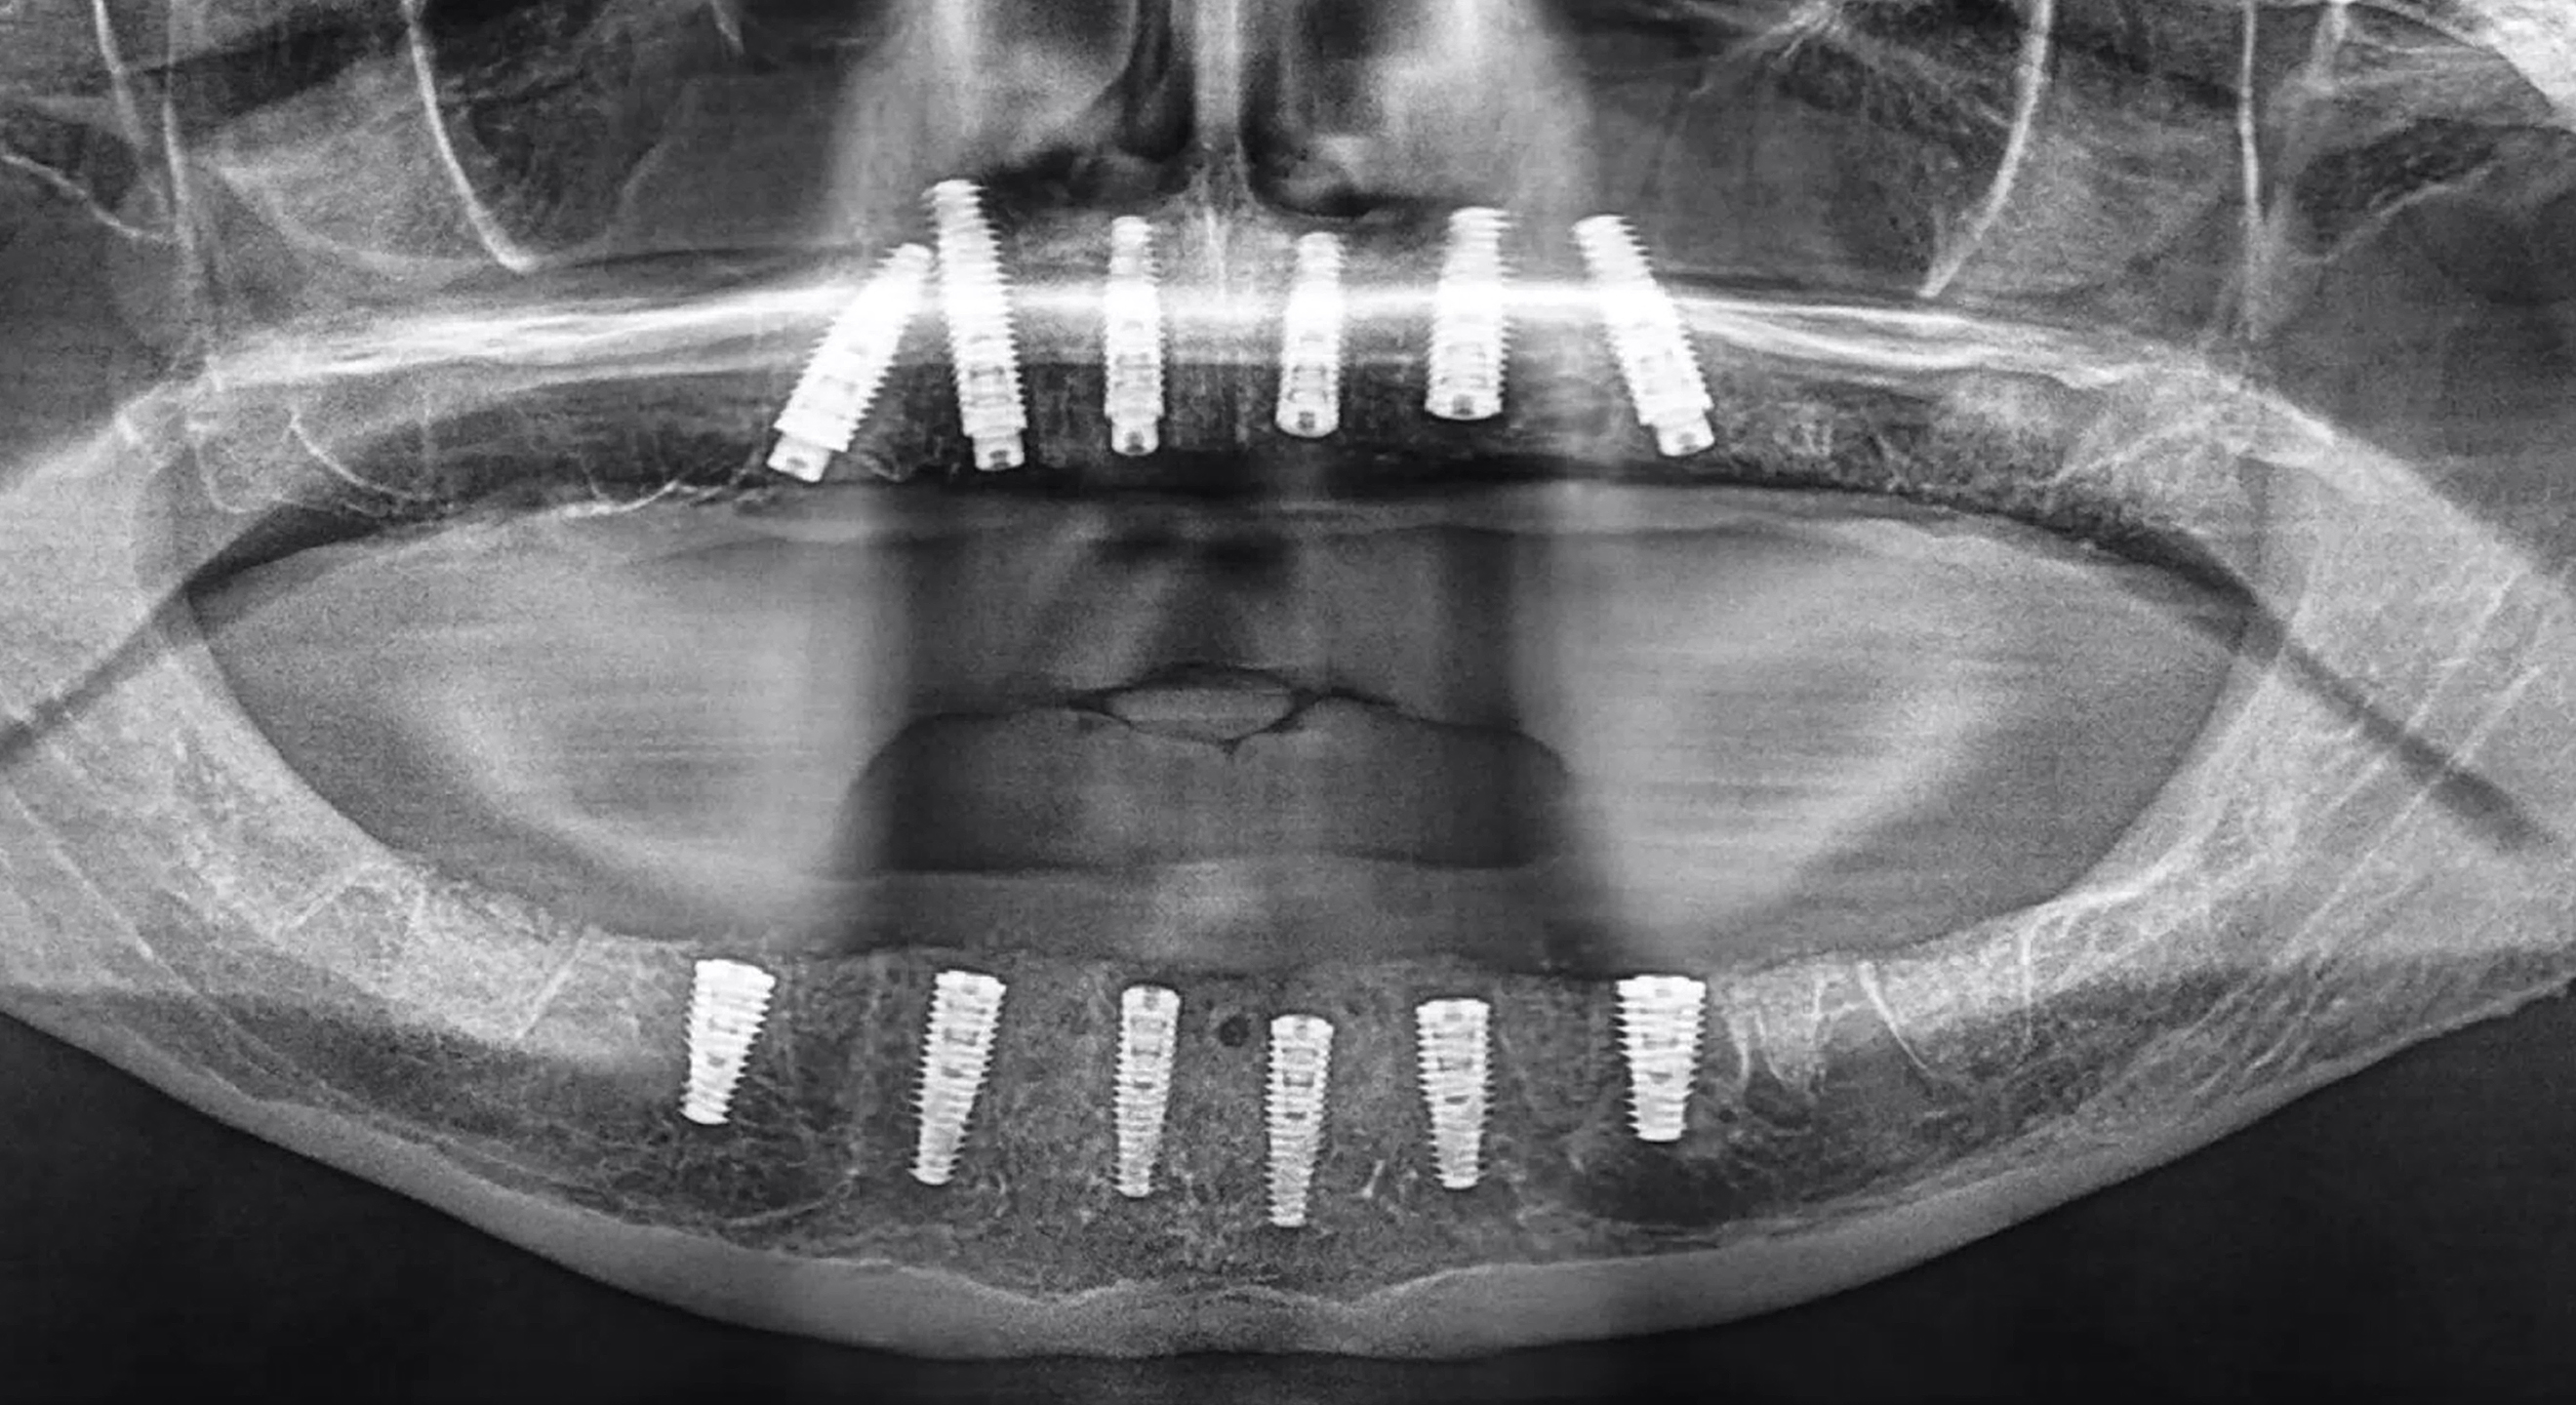

Fig. 17: Post-op panoramic radiograph revealing the successful placement of 12 implants in a two-stage protocol, requiring a healing period of three to four months before uncovering.

The mandibular bone reduction was completed using piezoelectric surgery (PIEZOSURGERY, mectron) and rotary instruments (Alveoplasty Surgical Kit, Meisinger) to provide adequate width and restorative space for the implant-supported restoration. Once the bone reduction had been completed, the bone-borne osteotomy guide was placed on to the mandibular ridge. The advanced AI-generated segmentation provided for an intimate fit of the guide, which was then secured with three horizontal anchor pins and guide stabilisers to immobilise the guide during the drilling process (Fig. 16a). Once the six implants had been successfully placed, the guide was removed, revealing the reduced bone and residual extraction sockets (Fig. 16b). Approximately 1 cm3 of mineralised cortical and cancellous bone was placed in the extraction sockets and remaining fenestrations. The implant stability quotient values were not adequate for immediate loading, and therefore, a two-stage protocol was chosen for the mandibular arch implants. The postoperative panoramic image revealed the successful placement of a total of 12 implants in both the mandibular and maxillary arches (Fig. 17).